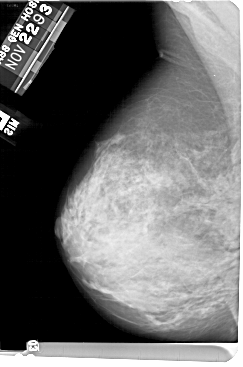

A_1504_1.LEFT_MLO

LEFT_MLO LINES 5491 PIXELS_PER_LINE 3631 BITS_PER_PIXEL 12 RESOLUTION 43.5 NON_OVERLAY